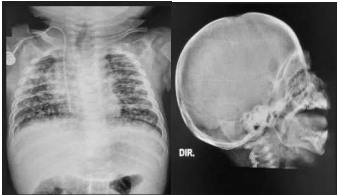

- RX tórax (vide imagem abaixo). *O laudo do radiologista evidenciou, entre outros achados, lesões osteolíticas em ambas as escápulas. Foi sugerido realizar RX de crânio (vide abaixo).